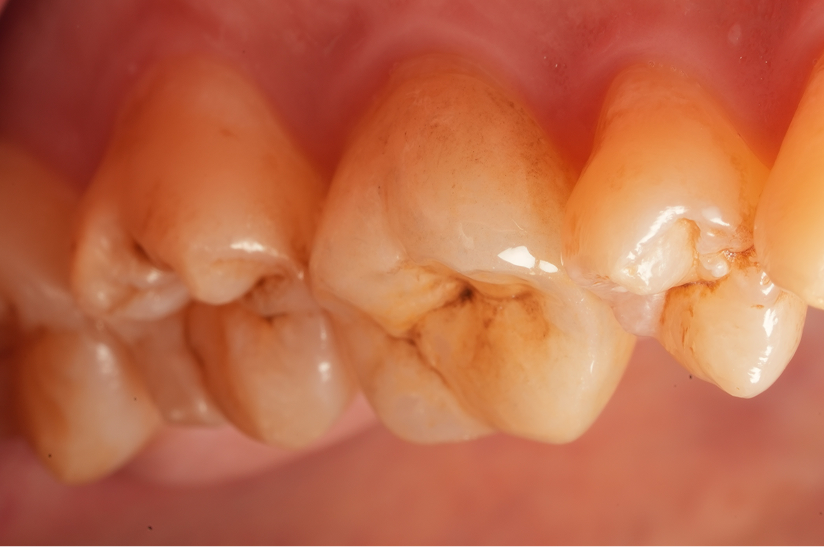

Before

After

主訴

噛むと違和感がある。

治療内容

リトリートメント(再根管治療・大臼歯)

ファイバーポストコア

治療期間

1ヶ月

治療費用

198,000

治療の

リスク

根尖部透過像が完全に消失しない可能性があります。